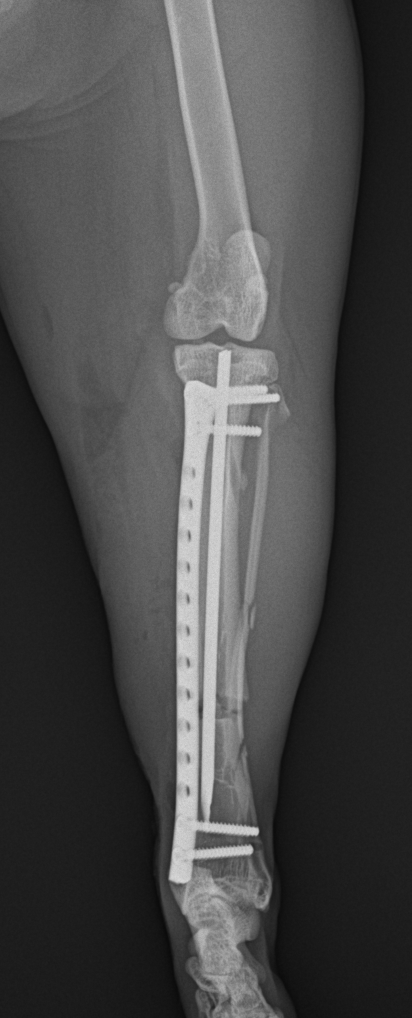

最小侵襲整形外科 脛骨を骨折した猫が足を痛がっているので手術して欲しいと主治医から連絡がありました。外科用イメージを使って、髄内ピンとプレートによる固定術を行い、翌日退院しました。この手法は皮膚や筋肉を大きく切開しないというメリットがあります。 症例カテゴリー 放射線治療整形外科軟部組織外科脳神経外科内科腫瘍外科救急・集中治療リハビリテーション科腫瘍内科内視鏡科脳神経科呼吸器外科中医・漢方猫の腎移植循環器科